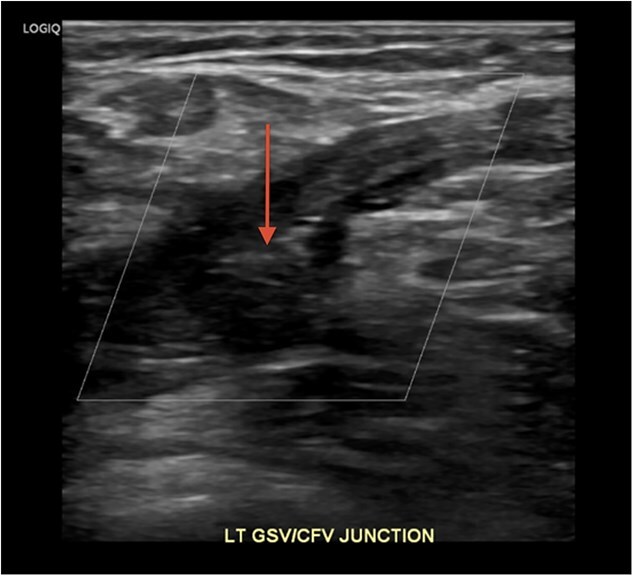

梅-瑟纳综合征(May-Thurner Syndrome, MTS)是由于左髂总静脉受压而导致深静脉血栓形成(DVT)。在深静脉血栓形成之前,MTS通常是无症状的。我们的病例是一名37岁的女性,她在最近的旅行和口服避孕药后出现左腿肿胀和疼痛。静脉双工超声证实深静脉血栓,CT血管造影排除肺栓塞。她接受了肝素抗凝治疗,并接受了机械取栓和支架置入术。她的症状在两天内得到改善,并在阿哌沙班和普拉维克斯的治疗下出院。该病例涉及一种独特的MTS患者表现,涉及一名患有不明原因左侧深静脉血栓的年轻女性,这种情况通常见于老年凝血障碍患者。

May-Thurner Syndrome (MTS) is caused by left common iliac vein compression, resulting in deep vein thrombosis (DVT). MTS is usually asymptomatic until DVT occurs. Our case features a 37-year-old woman who presented with swelling and pain in her left leg after recent travel and oral contraceptive use. Venous duplex ultrasound confirmed DVT and CT angiogram excluded pulmonary embolism. She received Heparin anticoagulation and underwent mechanical thrombectomy and stenting. Her symptoms improved within two days, and she was discharged on Apixaban and Plavix. This case involves a unique patient presentation of MTS, involving young woman with unexplained left-sided DVT, a scenario typically seen in older patients with clotting disorders.